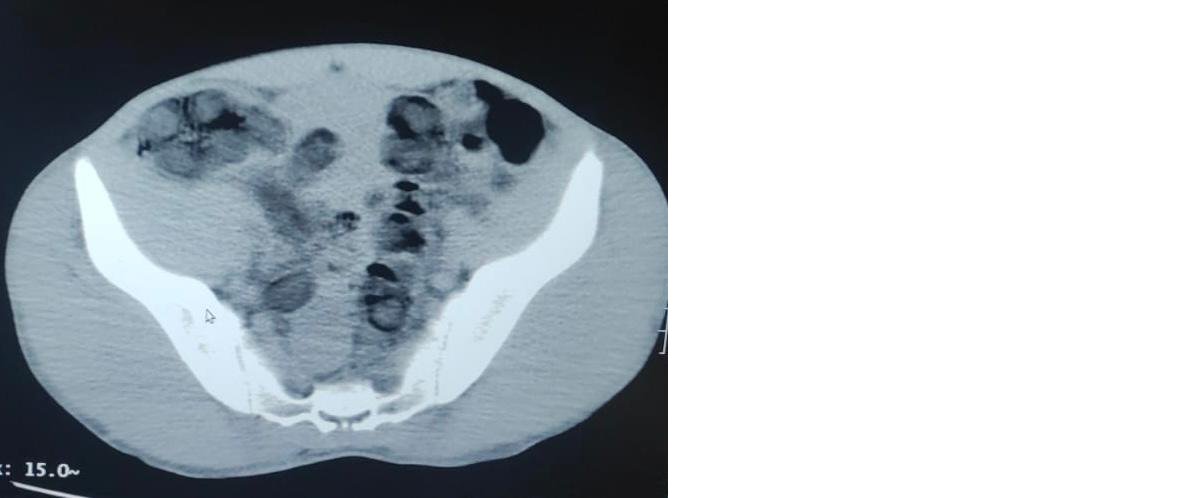

Doktorlar tarafından yapılan kontrollerde, şüphelilerin midesinde toplam 176 adet kapsül içerisinde 1 kilo 96 gram eroin çıktı. Jandarmadaki işlemlerinin ardından adliyeye çıkartılan 2 şüpheli, tutuklanarak cezaevine gönderildi.